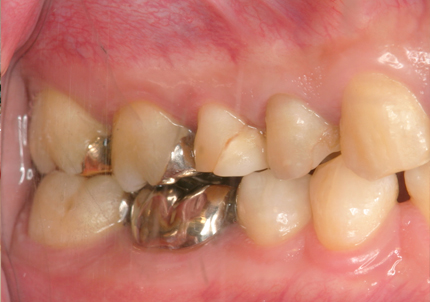

患者:Y.S 様

初診日 :2018年10月

主訴 :上顎前歯部審美障害、臼歯部補綴治療

1.初診時口腔内写真(2018年10月)